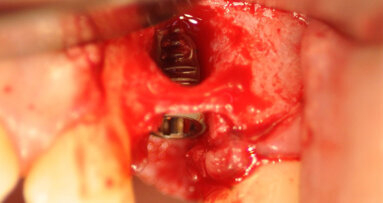

Chirurgia

Prima di estrarre gli incisivi, le corone 13 e 23 sono state rimosse e i denti sono stati preparati per l’applicazione di un ponte provvisorio. Con una ceratura sul modello della situazione e sui pontic, è stata creata una forma ottimale per supportare e modellare il tessuto mole durante la fase di guarigione. Nello stesso tempo, il ponte provvisorio funziona come copertura della ferita se non è possibile la chiusura primaria (Figg. 3-6)1-4. Nella fase successiva, i denti da 12 a 22 sono stati estratti. Il contorno del lembo risparmiava la papilla mediana e quella mesiale su 12 e 22. A causa dei difetti ossei interprossimali, lo scollamento della papilla in questa regione avrebbe portato a gravi recessioni. I difetti ossei verticali, soprattutto tra 11 e 12, erano ovvi dopo lo scollamento del lembo a tutto spessore. Sono state eseguite incisioni di rilascio distalmente ai canini e solo nella gengiva aderente per evitare la formazione di cicatrice attraverso tagli verticali nella mucosa. Il vestibolo basso rendeva meno logico uno lembo a spessore parziale o a tasca periostale. Mobilizzando il tessuto molle dalle labbra mediante altri design di lembo porterebbe a limiti funzionali, tensione della sutura e plastica gengivale secondaria per riposizionare il tessuto molle coronale tras-posizionato. I margini della ferita sono stati ridefiniti per rimuovere l’epitelio prolungato e i difetti ossei liberati dalla crescita interna del tessuto molle (Figg. 7-10). La perdita di osso orizzontale era moderata. Gli impianti sono stati posizionati leggermente sottocrestali. Sebbene il gap tra gli impianti e il piano buccale fosse circa 1-1,5 mm e lo spessore del piano buccale 1-1,5 mm a causa del riassorbimento, abbiamo optato per impianti 3,8 mm, lasciando un gap di 1,5 mm al piano buccale5-10. Lo spazio interimplantare e il piano buccale sono stati incrementati con una combinazione di alloinnesto e xenoinnesto. Lo xenoinnesto è stato applicato anche sul piano buccale, in modo da manipolare il riassorbimento del piano buccale. Come barriera è stata utilizzata una membrana di pericardio (Fig. 11). L’anatomia dell’arcata superiore e il vestibolo basso non permettevano una chiusura primaria. Per proteggere la membrana dal riassorbimento proteolitico e l’incremento, abbiamo applicato due strati di tessuto sulla membrana. Attraverso lo strato di collagene e la protezione del ponte provvisorio, dopo due settimane ci si aspettava granulazione libera della copertura dell’alveolo estrattivo (Fig. 12)11,12.